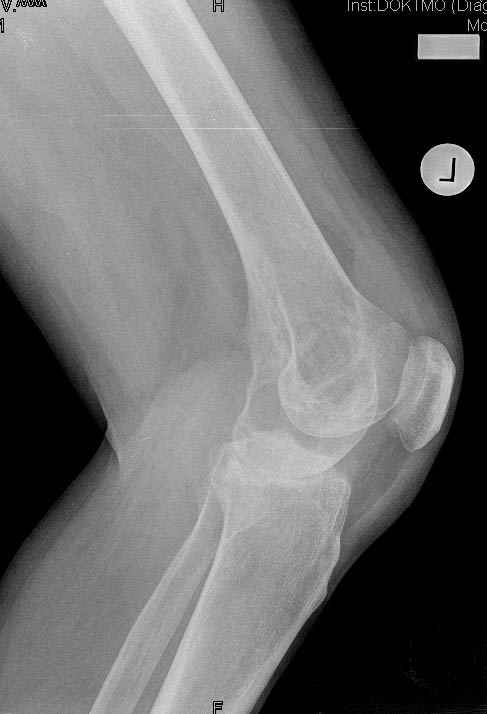

Коллеги!Окажите, пожалуйста, консультативную помощь.Мужчина, 41 год, 15 лет состоит на учете по поводу ревматоидного полиартрита, гормонзависимый (преднизолон получает нерегулярно). В процесс вовлечены крупные и мелкие суставы. 01.01.06 - без травмы наступил патологический перелом на границе н/3-с/3 бедра (перелом на фоне кистозных изменений?) Биопсия из зоны перелома - <реактивные изменения в очаге перелома>, без признаков опухоли. На рентгенограммах, помимо перелома, кистозные изменения на мыщелках б/берцовой кости и мыщелке бедра с другой стороны. До травмы со стороный коленных суставов был болевой синдром, функция практически в полном объеме. Какие будут предложения по тактика лечения перелома и кист на противоположом бедре? Заранее благодарю! С уважением, А.В.Владзимирский Донецкий НИИ травматологии и ортопедии Донецк, Украина